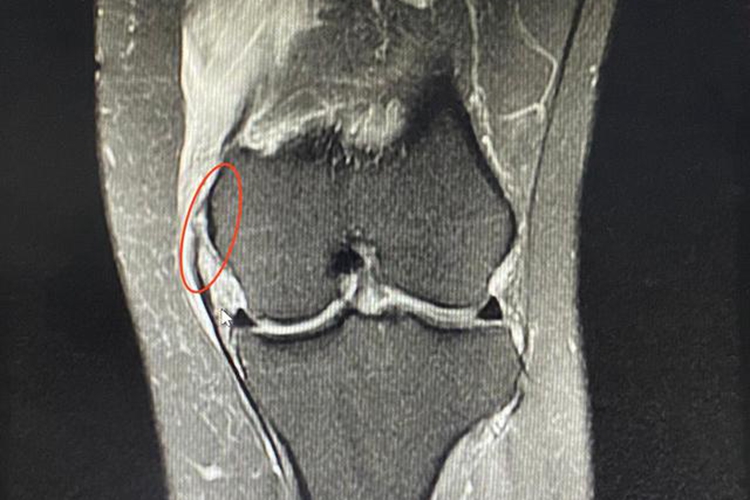

内侧副韧带损伤:表现为膝盖内侧常突发剧痛,但又可迅速减轻,仍可继续运动,随后疼痛又逐渐加剧,且疼痛仅局限于膝盖的内侧。

内侧副韧带损伤:在膝关节外侧受强大暴力打击或重压的冲击,可使膝关节过度外翻而损伤内侧副韧带,也可因为膝关节在屈曲位时,小腿突然外展、外旋,或在足部固定时,大腿突然内收、内旋而发生膝部内侧副韧带损伤。

内侧副韧带损伤:对于单纯内侧副韧带损伤一般采用非手术治疗。一度损伤仅需对症治疗,扶拐1-2周;二度损伤需要夹板或石膏固定,扶拐2-3周;三度损伤需要夹板或石膏固定后扶拐4-6周,早期行功能锻炼。